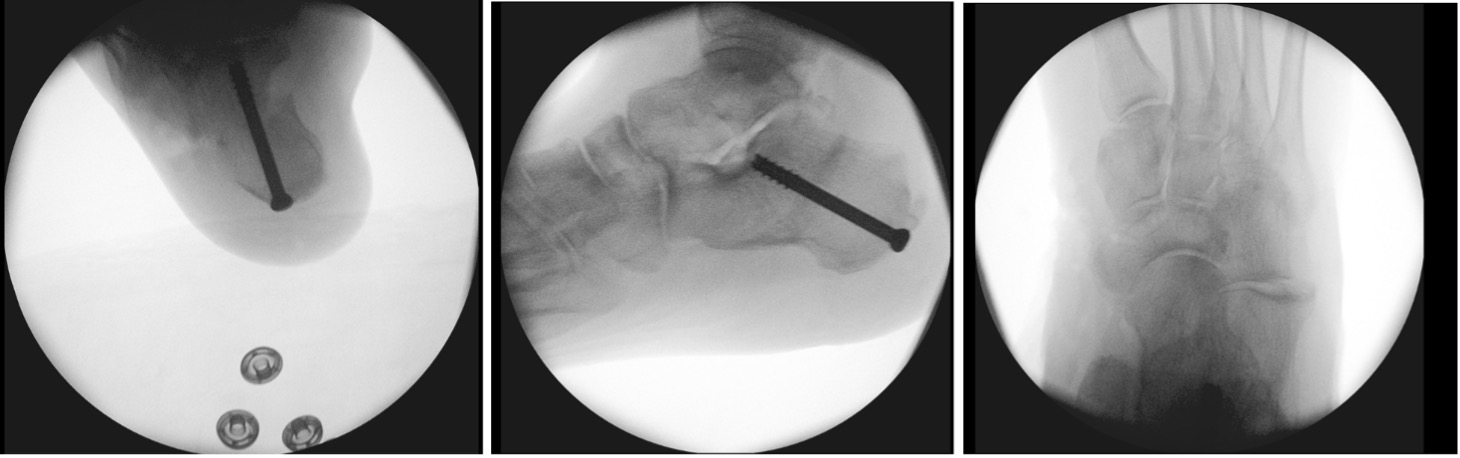

Stage IIA: Medialising calcaneal osteotomy + FDL transfer (Fig 9,10)

Figure 9: FDL transfer into navicular bone after tibialis posterior debridement

Figure 10a: Intra-op images (of Figure 7) showing calcaneal shift and correction of alignment